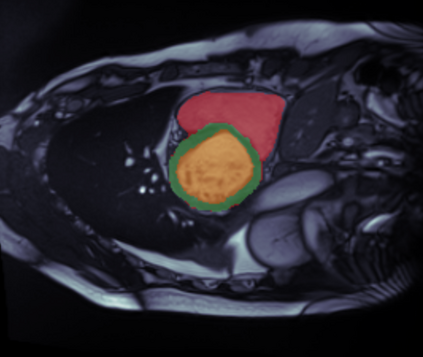

Supervised machine learning provides state-of-the-art solutions to a wide range of computer vision problems. However, the need for copious labelled training data limits the capabilities of these algorithms in scenarios where such input is scarce or expensive. Self-supervised learning offers a way to lower the need for manually annotated data by pretraining models for a specific domain on unlabelled data. In this approach, labelled data are solely required to fine-tune models for downstream tasks. Medical image segmentation is a field where labelling data requires expert knowledge and collecting large labelled datasets is challenging; therefore, self-supervised learning algorithms promise substantial improvements in this field. Despite this, self-supervised learning algorithms are used rarely to pretrain medical image segmentation networks. In this paper, we elaborate and analyse the effectiveness of supervised and self-supervised pretraining approaches on downstream medical image segmentation, focusing on convergence and data efficiency. We find that self-supervised pretraining on natural images and target-domain-specific images leads to the fastest and most stable downstream convergence. In our experiments on the ACDC cardiac segmentation dataset, this pretraining approach achieves 4-5 times faster fine-tuning convergence compared to an ImageNet pretrained model. We also show that this approach requires less than five epochs of pretraining on domain-specific data to achieve such improvement in the downstream convergence time. Finally, we find that, in low-data scenarios, supervised ImageNet pretraining achieves the best accuracy, requiring less than 100 annotated samples to realise close to minimal error.